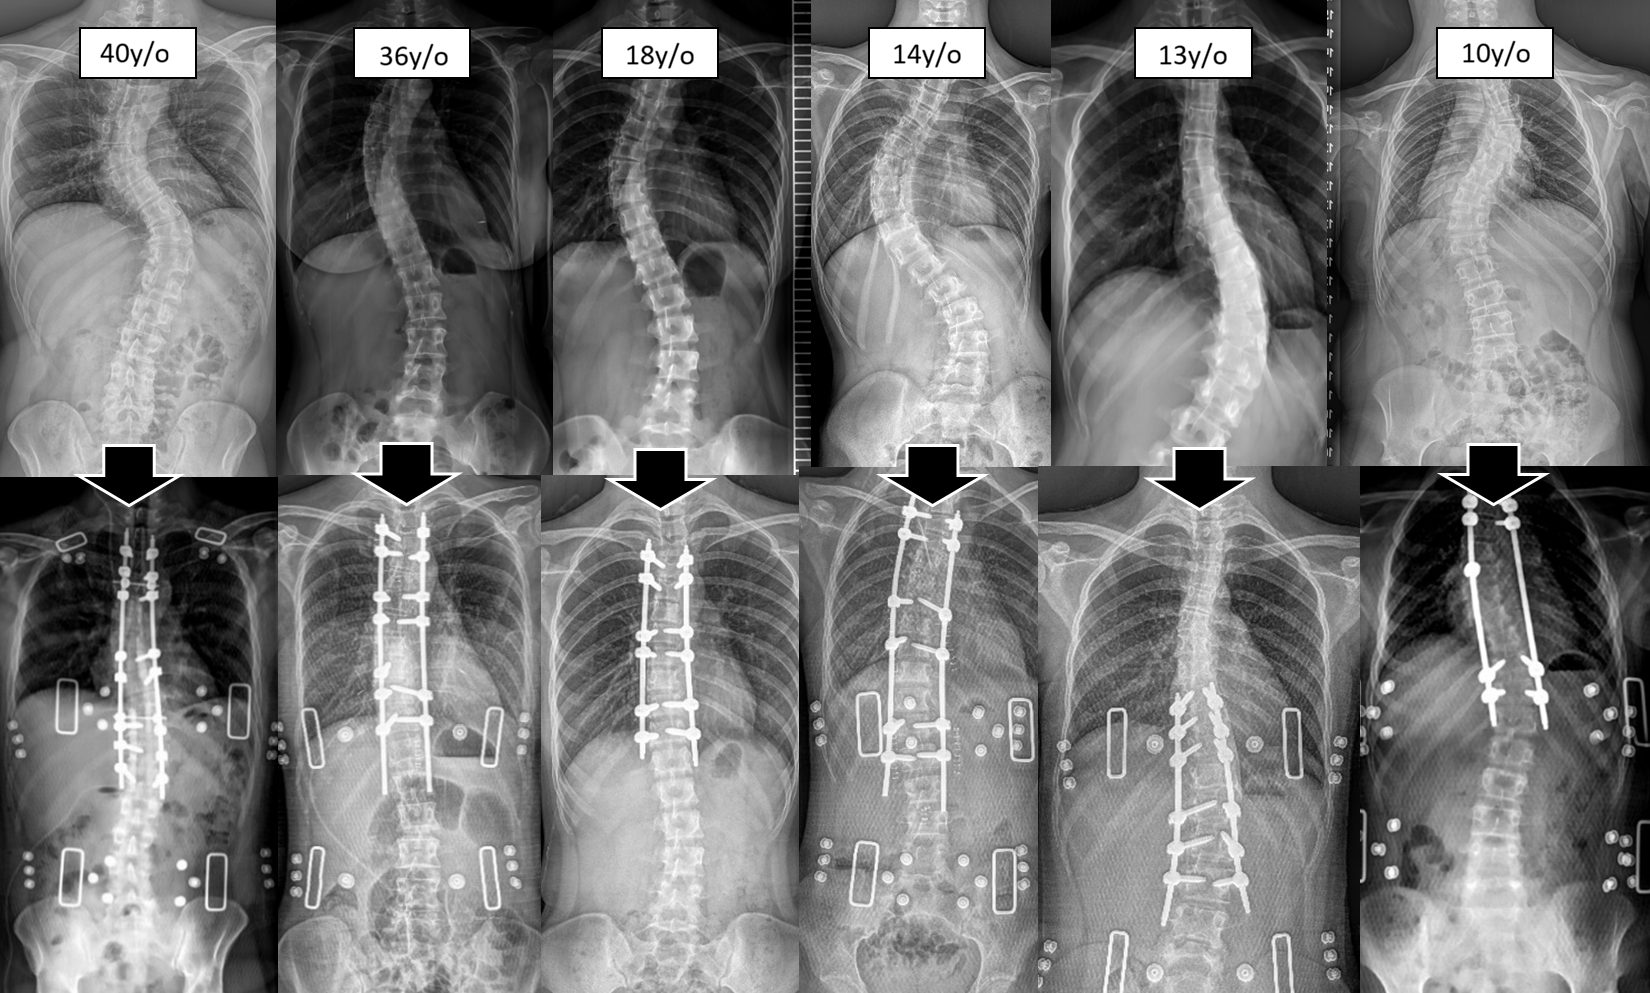

2. The "Golden Window" for Undergoing Scoliosis Surgery

The timing of surgery directly impacts the correction rate and recovery speed. Clinically, there are two key windows:

The Adolescent Golden Window (Before Skeletal Maturity):

The optimal time for intervention is typically at Risser Sign 3-4 (when the pelvic growth plates are nearly fused), if the Cobb angle has already reached the surgical threshold. At this stage, the spine retains a degree of flexibility. This allows surgeons to achieve greater angular correction with less corrective force, and post-operative bone fusion occurs very rapidly. -

The Adult Critical Window (Before Symptom Decompensation):

For adult patients, the surgical timing is determined not by age, but by intervening before "decompensation" occurs. Surgery should be considered when scoliosis leads to significant trunk imbalance, worsening pain, or a reduced walking distance (claudication). The goal is to prevent long-term spinal imbalance from accelerating degeneration in adjacent spinal segments.

3. For Growing Children: Growth-Guided Scoliosis Correction Surgery

For children under the age of 10 with early-onset scoliosis whose skeletons have not yet matured, the goal is "to control the curvature while allowing for spinal growth."

Extendable Connecting Rods: Following the initial surgery, regular follow-up is required. Once the patient has passed through the growth period, permanent fixation can be achieved through a final surgical procedure.